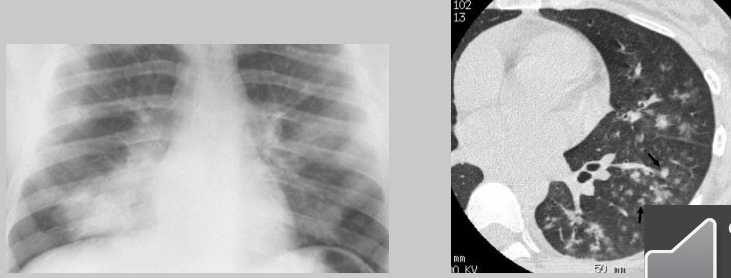

Describe the RA of bronchopneumonia

inflammation produces small patches of consolidation throughout the lungs — no air bronchograms present

Describe the RA of interstitial pneumonia

mesh-like shadows resulting from linear or reticular opacities — untreated can lead to “honeycomb lung” or cystic spaces as demonstrated by CT